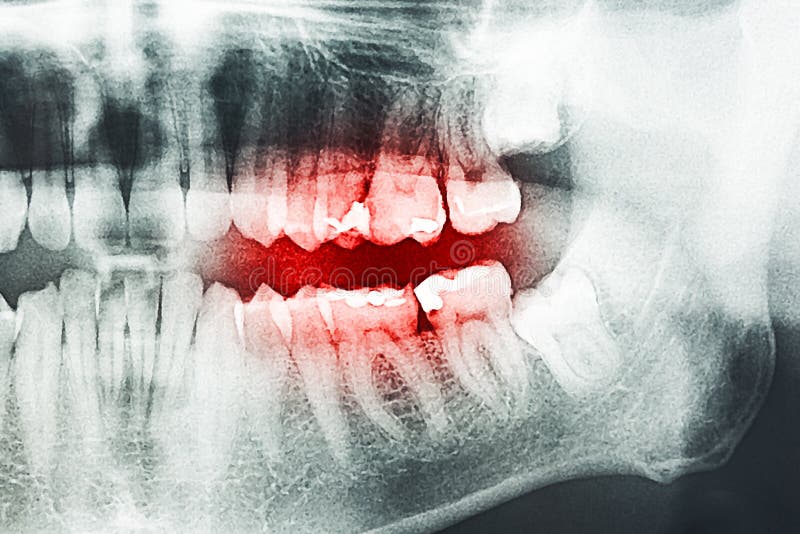

Tooth Pain on XRay stock photo. Image of head, health 46715332 Tooth Pain After X Ray If you've a toothache but your dentist says nothing is wrong, it could be the surrounding soft and hard tissues that are referring pain to your teeth. Due to their close proximity, your body may be confused and perceive it as a toothache while it is actually something else. The second most common cause is a cracked tooth. Sometimes, tooth. Tooth Pain After X Ray.

From www.capstonedental.com.au